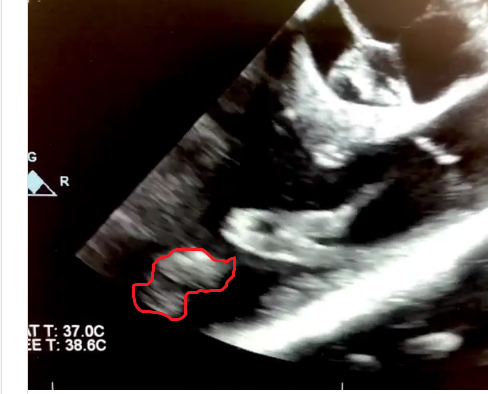

Lead extraction and goobers case.

Not sure if clips are uploading. Hopefully they are.

Comments, concern, plan?

As far as thrombus burden, granted we only have one view to look at but we do need to consider that that thing is totally enveloping multiple centimeters of the distal part of that lead. I'm thinking about it like a vine wrapping up a telephone pole. The vine has a pretty slim profile as is but imagine how much plant mass you have if you stripped it off the pole and bunched it up.

Not to mention it looks like there's a good bit of secondary non-mobile thrombus that may be distinct from the mobile schmutz on the lead that's catching everyone's eye (see below between the red arrows).

As per this particular patient, the thrombus is a monster and was literally ebb and flowing in and out of the pulmonary valve. There is no doubt in my mind that if this thing were to embolize, it would cause harm. Not only is it large, but certain aspects of it are very well organized and would not be easy to tpa if it ended up in the lungs. That being said, the patient was 30 years old and had no other heart issues (good EF, etc).

Ultimately, cardioligy struggled getting this thing out (had 20 years to bury itself into a developing heart). Cards became very reluctant to pursue the lead once i showed him what we were dealing with. This particular cardiologist starts to think of surgical intervention once it is 3-4cm in size. TEE demonstrated at least a 7 cm mass which was likely even bigger. Cards persisted in trying to get it out until his lead extender/sheath broke off at which point the solution became obvious. Pump run for lead extraction which in all honesty would have been a good choice from the get-go as we had an otherwise healthy patient/good protoplasm. Downside would be the scar in a young patient. TPA or anticoagulants were not going to dissolve the proximal thrombus and in the meantime he was at risk for a major card/pulm risk.